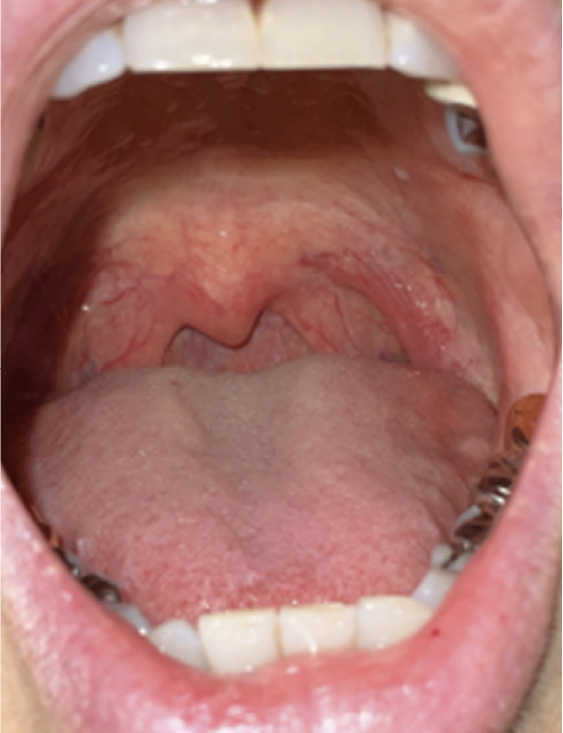

治療前

治療後

• 症例写真

診察上マランパチー3 舌:比較的大きい

肥満はないが年齢が比較的若いわりに気道が狭く、舌も大きいためDual Deep Thermiaの良い適応と考えられた。